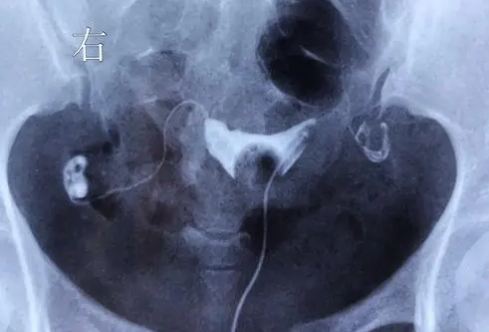

輸卵管檢查是通過特定的醫(yī)療設備對女性生殖器官進行內窺鏡檢測和造影術來確定是否存在輸卵管問題。這個過程可以通過腹腔鏡、盆腔鏡等方式進行。